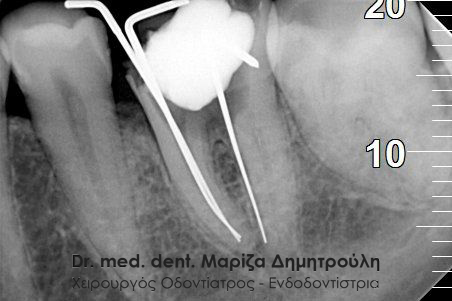

Έγινε η κλινική και ακτινογραφικά εξέταση του δοντιού. Στην αρχική ακτινογραφία που πραγματοποιήθηκε πριν τη διάνοιξη του δοντιού παρατηρήθηκε ο έντονος εκτροχισμός του δοντιού ανάμεσα στις ρίζες. Η ακτινογραφική αυτή εικόνα γεννά υποψίες για πιθανή διάτρηση του δοντιού στο συγκεκριμένο σημείο. Διάτρηση ενός δοντιού κατά τη διάρκεια της απονεύρωσης μπορεί να προκληθεί όταν ο οδοντίατρος “ανοίγει” (τροχίζει) το δόντι στην προσπάθεια του να εντοπίσει τις ρίζες του δοντιού (ριζικοί σωλήνες). Είναι δηλαδή πιθανόν το δόντι να τροχιστεί σε άλλο σημείο από αυτό που εντοπίζονται οι ρίζες του δοντιού, με αποτέλεσμα να δημιουργηθεί μία τρύπα στο δόντι. Η τρύπα αυτή ονομάζεται διάτρηση.

Μετά από τη χορήγηση τοπικής αναισθησίας και την τοποθέτηση ελαστικού απομονωτήρα ακολούθησε η διάνοιξη του δοντιού. Αμέσως μετά την αφαίρεση του προσωρινού σφραγίσματος παρατηρήθηκε έντονη και απότομη αιμορραγία του δοντιού, η οποία προερχόταν από ένα συγκεκριμένο σημείο. Η κλινική αυτή εικόνα επιβεβαίωσε τις υποψίες για διάτρηση του δοντιού. Εντοπίστηκε το σημείο της διάτρησης και έγινε έλεγχος με μία ακτινογραφία. Στη συνέχεια πραγματοποιήθηκε η αποκατάσταση της διάτρησης με ειδικό υλικό και εντοπίστηκε ο τρίτος σωλήνας του δοντιού. Η όλη διαδικασία επιβεβαιώθηκε με τη λήψη ακτινογραφίας.

Επιβεβαίωση της διάτρησης

Εντοπισμός του τρίτου ριζικού σωλήνα